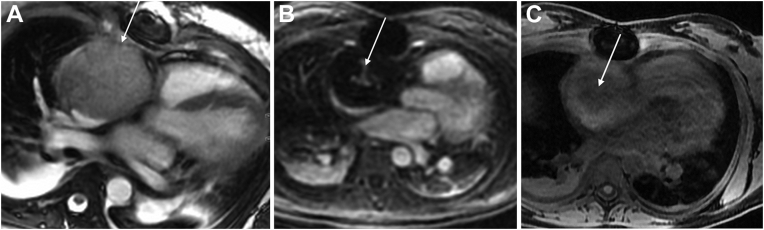

Figure 2.

Contrast-enhanced CT of the chest reported to be performed as a pulmonary arterial embolism protocol was obtained to rule out pulmonary embolism. It shows a large solid mass in the right atrium (arrows) in the (A) axial, (B) coronal, and (C) sagittal planes.

A 23-year-old woman (G2P0202) with no medical history presented to the emergency department 5 days after a normal spontaneous vaginal delivery reporting chest pain, headaches, and vision changes and was found to have markedly elevated blood pressure. Given concern for preeclampsia with severe features and/or pulmonary embolism, the patient was admitted to the hospital and started on a magnesium drip and intravenous medications for blood pressure control. Notable laboratory studies included elevated brain natriuretic peptide (1,168 pg/mL) and mildly elevated troponin I (0.07 ng/mL). Otherwise, the complete metabolic panel was normal, including normal aminotransferase levels. Electrocardiography showed normal sinus rhythm (Figure 1). Contrast-enhanced computed tomography (CT) of the chest reported to be performed as a pulmonary arterial embolism protocol excluded pulmonary embolism but revealed a large solid mass (6.4 × 6.5 × 6.6 cm) in the right atrium with reported central contrast enhancement versus calcification (Figure 2). Subsequent transesophageal echocardiography reportedly confirmed the presence of a large mass occupying the entire right atrium and impinging on the tricuspid valve, although these images were not available to us for review. Given these findings, the patient was transferred to a hospital with cardiac surgery for planned excision of the mass.